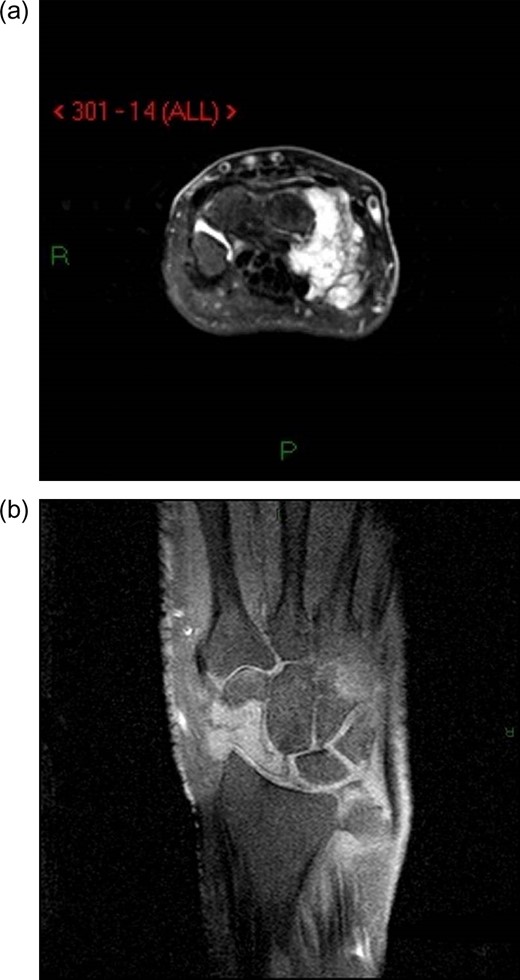

Radiographs of the right hand and wrist revealed a lytic lesion in the scaphoid with nearly complete destruction of the distal pole (Fig. 1a–c). The lateral radiograph also demonstrated some abnormal scalloping of the distal radius articular surface (Fig. 1c). Magnetic resonance imaging (MRI) showed destructive changes of the radial sided carpus (Fig. 2a and b), suggestive of neoplastic or infectious processes, but was inconclusive.